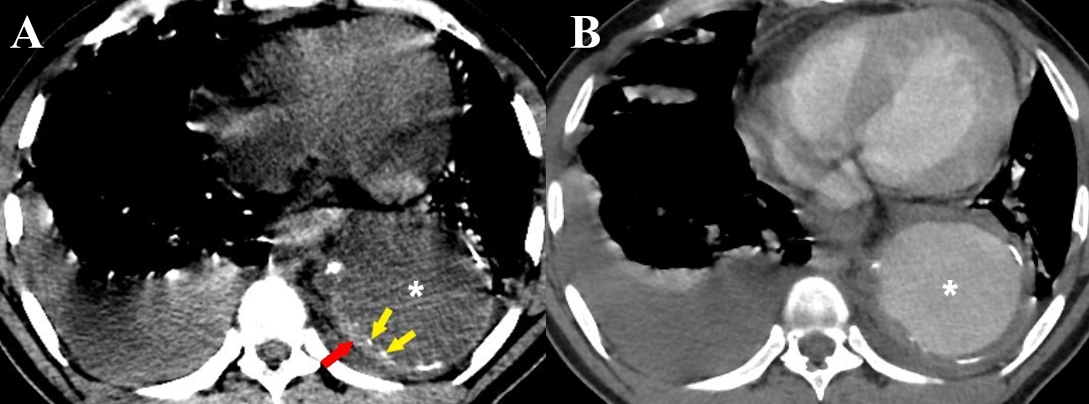

CT is an excellent imaging modality for the diagnosis of IMH with sensitivity and negative predictive value approaching 100%. Non-contrast CT is extremely useful in the diagnosis of IMH [9]. On non-contrast CT, IMH is seen as a crescentic hyperdense (60-70 HU) thickening within the aortic wall, usually more than 7mm in diameter but generally less than 15mm (Figure 10a).4,8,9,24,25 Intimal calcifications, if present, can be seen displaced inwards, differentiating it from a mural thrombus.9,24,25 The majority of IMH involve the descending aorta.4

On contrast-enhanced CT, the crescentic thickening remains unenhanced (Figure 10b). IMH is characterized by the absence of intimal disruption which is the characteristic feature of AAD. Parameters to be included in an ideal report of IMH have been summarized in (Table 4).

Figure 10 a-b Intramural hematoma. (a) Axial non-contrast CT thorax image in a case of thoracic aortic aneurysm (white asterisk) shows a crescentic thickening of high attenuation within the wall of the descending thoracic aorta (red arrow). Intimal calcifications are seen displaced inwards (yellow arrows). (b) A contrast-enhanced CT thorax image of the same patient shows no enhancement of the IMH. Bilateral pleural effusions are also seen in both images (a) & (b).